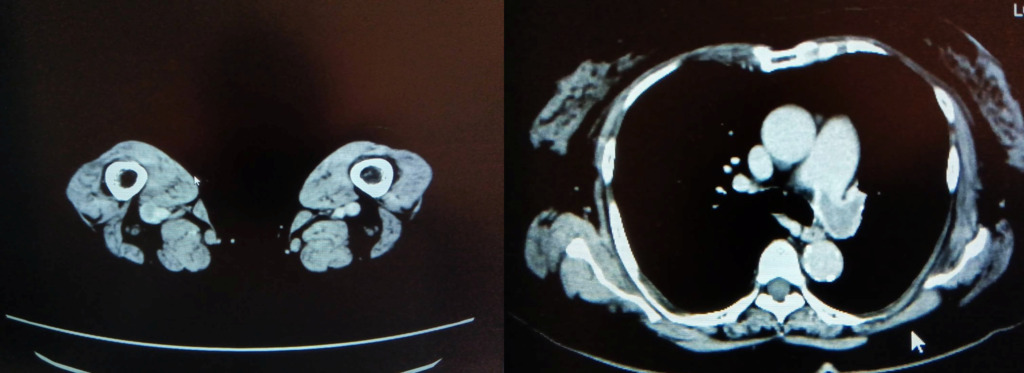

冠動脈に有意な狭窄はなかったのですが、先ほどの症例と同じように

肺動脈にfillifng defectを認めます。

造影後”15分後”に追加で撮影した画像がこちらです。

造影後15分後でも造影効果がわずかに残っていました。

これを見ると、冠動脈CTでは右肺動脈に大きい血栓があるように見えましたが、左肺動脈の方が血栓サイズが大きく、これによる左胸の痛み症状だったのではないかと考えられました。

下肢静脈も15分後でもわずかに造影効果が残っており、左浅大腿静脈にfilling defectを認めました。

造影剤量も60mlと通常の深部静脈を観察するには少ない量でしたが、15分後の撮影でもなんとか観察することができました。

こちらも管電圧を下げて撮影しました。時間経過で造影効果が低くなった肺動脈や深部静脈の造影効果を上げてなんとか観察することができた症例です。